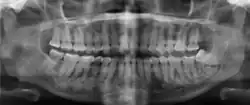

Florid osseous dysplasia of the mandible

Diagnostic methodX-ray, CBCT scan, vitality testing of teeth

Diagnosis is based on clinical and radiographic observations, and in rare cases, biopsy may be performed.[3] Diagnosis is important so that the treating doctor does not confuse it for another periapical disease such as rarefying osteitis or condensing osteitis. Incorrect diagnosis could lead to unnecessary root canal treatments, or biopsy or surgical intervention which can be invasive and increase the risk of infection.[5] A pulp vitality test such as a cold test or electric pulp test can aid in diagnosis, since COD generally does not compromise pulp vitality.[6] COD can be found in individuals of all ages and ethnic backgrounds, but it has been observed more frequently in individuals of African, East Asian, and Asian descent.[7] Cone-beam computed tomography (CBCT) has proven useful in distinguishing between COD and periapical cysts, when examined with quantitative texture analysis using specialized software.[5]

xray and CBCT scans of periapical cemental dysplasia